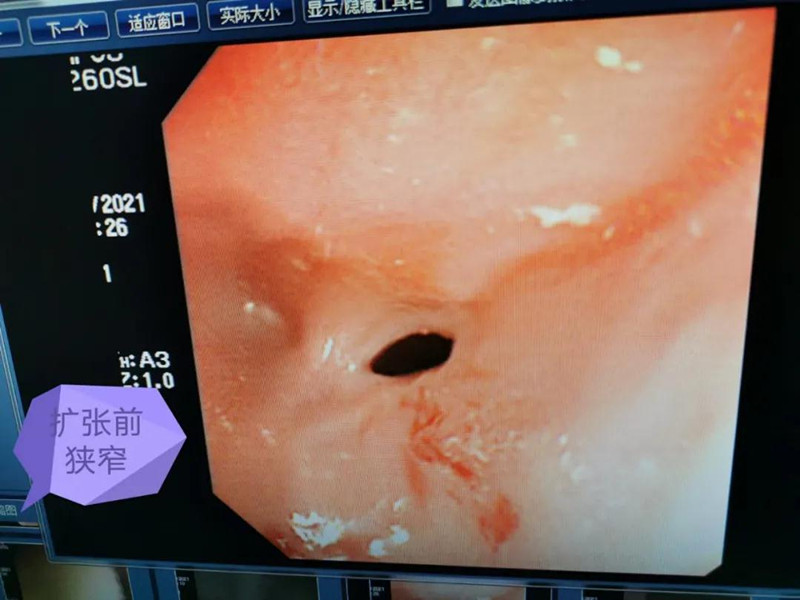

天天6个月了。最近总出现呛奶的情况,后来还出现肺炎症状。在啪啪网 经食道造影后,医生发现天天的症状是由术后并发症“食道吻合口狭窄”引起的,最窄处仅5mm多一点。食道狭窄球囊扩张术是目前最适合天天的手术了。内镜中心副主任边鹏说,这是一种微创介入治疗,具有创伤小、恢复快、合并症少的优势。2月26日,在麻醉科、内镜中心团队的合作下,边鹏为天天行经内镜下食道狭窄球囊扩张术。术中,边鹏用直径8mm的球囊进行扩张,将原来狭窄的食道扩成直径8mm的宽度。

天天太小,在球囊扩张的过程中,需要格外注意,不能扩张太快,否则会出现穿孔或大出血。所以边鹏每扩张3分钟,暂停3分钟,共扩张了3次。整个扩张过程很顺利,效果也非常好。次日,天天就出院了。在球囊扩张前,小儿内镜下显示,天天食道吻合口狭窄处上端竟有一团纸,家长也不清楚孩子是什么时候吃了纸。因为吻合口处太窄,纸下不去,形成了阻隔,导致天天最近总呛奶,奶汁进入气道,最终出现肺炎。